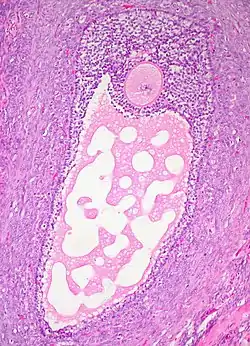

In case an ovarian cyst is surgically removed, a more definite diagnosis can be made by histopathology:

TypeSubtypeTypical microscopy findingsImage

Functional cystFollicular cyst

Corpus luteum cyst

• A convoluted cyst lining of luteinized granulosa cells[18]

• A prominent inner layer of fibrous tissue[18]

• An outer layer of theca cells[18]